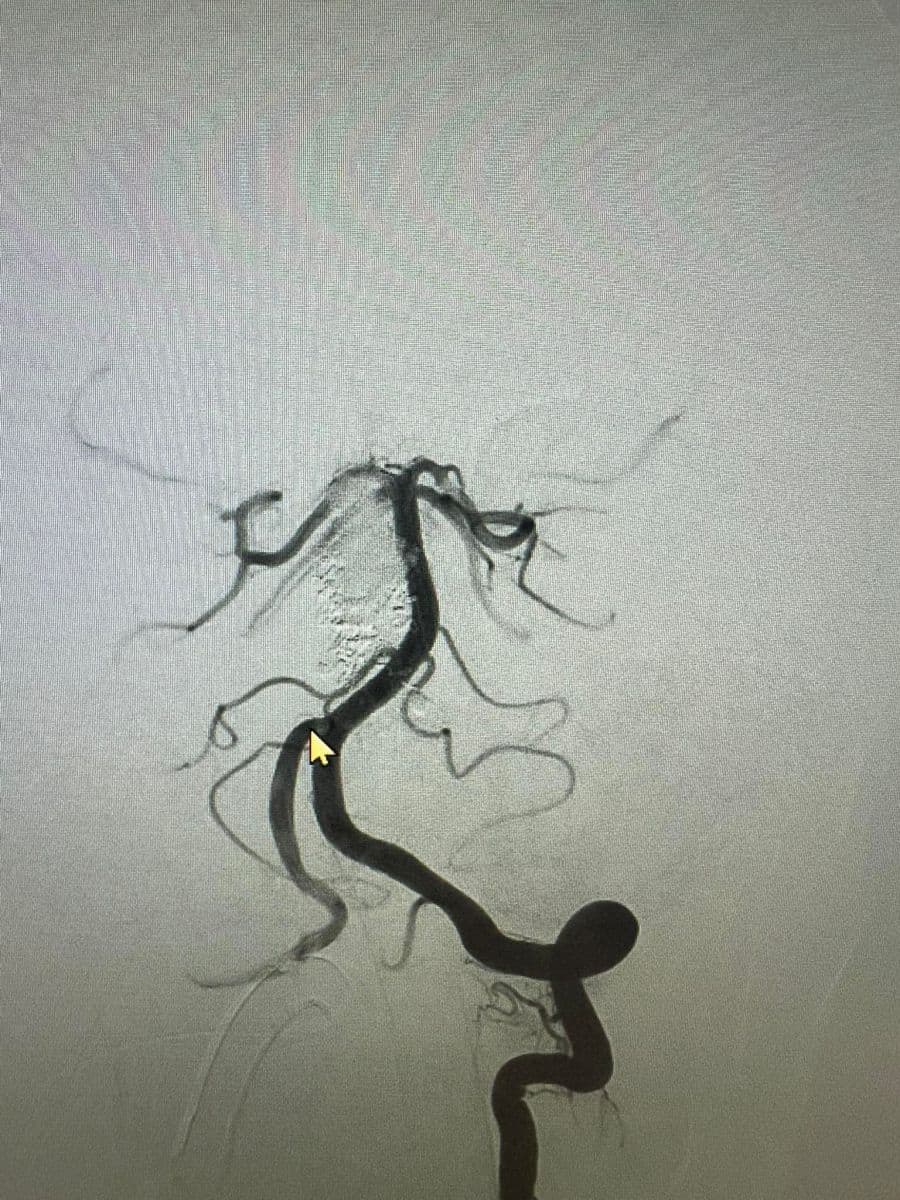

Δια ζώσης συμμετοχή των φοιτητών του Πανεπιστημίου Πατρών σε εξειδικευμένες τεχνικές ενδοαγγειακής αντιμετώπισης αγγειακών δυσπλασιών του κεντρικού νευρικού συστήματος.

Στην επέμβαση συμμετείχαν ο Καθηγητής Ενδοαγγειακής Νευροχειρουργικής Κος Β. Παναγιωτόπουλος, ο Καθηγητής Επεμβατικής Νευροακτινολογίας κος Π. Ζαμπάκης, ο επιμελητής επεμβατικής ακτινολογίας κος Μ. Θεοφάνης και ο αναισθησιολόγος κ. Γούδας.